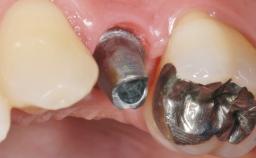

Treatment of Peri-Implant Mucositis at a Zirconia Implant

Frank Schwarz, Ausra Ramanauskaite

Recent clinical studies, most with short-to-medium term observation periods, have reported on the favorable clinical performance of zirconia implants in terms of survival rates, clinical, and radiographic outcomes (Roehling and coworkers 2016; Roehling and coworkers 2017; Rodriguez and coworkers 2018; Lorenz and coworkers 2019). Nonetheless, a rather high incidence of peri-implant disease at zirconia implants (39% of implants) was noted throughout a two-year period, highlighting the need for treatment protocols of peri-implant diseases at zirconia implants (Becker and coworkers 2017).